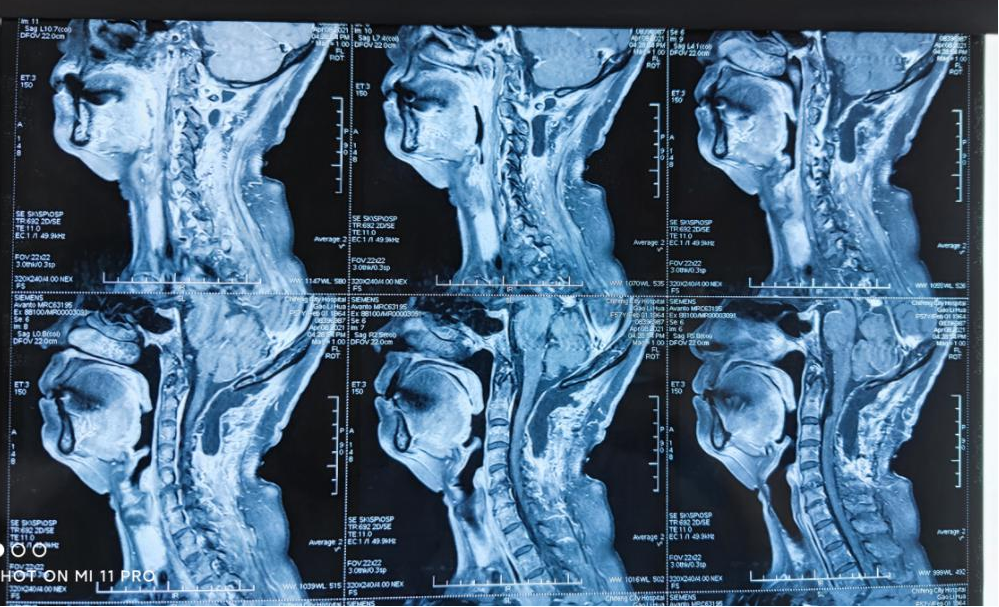

颈椎MRI显示,颈1、颈2水平椎管内髓外硬膜下多发占位。颈1水平肿瘤直径约1.0×1.1cm2,位于颈髓左侧,强化明显。颈2水平肿瘤直径约1.2×2.7cm2,位于颈髓右腹侧,不均匀强化,向右伸入右侧椎间孔,右侧椎间孔扩张,颈髓受压明显左移。神志清楚,双上肢浅感觉障碍,双下肢深浅感觉障碍,双上肢肌力肌张力正常,双下肢肌力Ⅳ级,肌张力弱。

颈1水平肿瘤

颈2水平肿瘤

术后颈椎MRI